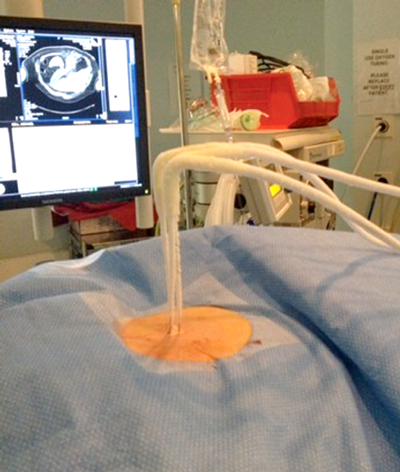

Under imaging guidance a series of cryoprobes are placed into the target lesion with the patient in the prone oblique position. Often this is performed under general anaesthetic with CT guidance, and this is our method of choice. We believe CT offers the most accurate depiction of the tumour and treatment boundaries in all planes, and permits precise probe placement with tolerances of 3-4mm. MRI is also set to evolve as an effective and robust guidance tool in the next few years. The size and morphology of the tumour dictates the number of probes required and their configuration (Figure 2). Broadly speaking, the probes should be placed approximately 1cm from the tumour edge and less than 2cm apart.

Figure 2: Probe placement.